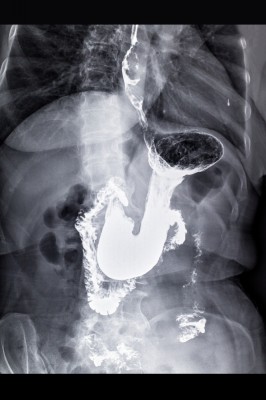

These are potential cancer symptoms: Change in bowel or bladder habits A sore that does not heal Unusual bleeding or discharge Thickening or lump in the breast or elsewhere Indigestion or difficulty in swallowing Obvious change in a wart or mole Nagging cough or hoarseness. Symptoms Warning Signs of Cancer Cleveland Clinic Signs of Cancer. No matter your age or health, its good to know the possible signs of themselves, they arent enough to diagnose the disease. If you have any of these signs, see your doctor. People should see a doctor if they have any new symptoms or existing symptoms worsen.

Signs and Symptoms of Cancer Do I Have Cancer?